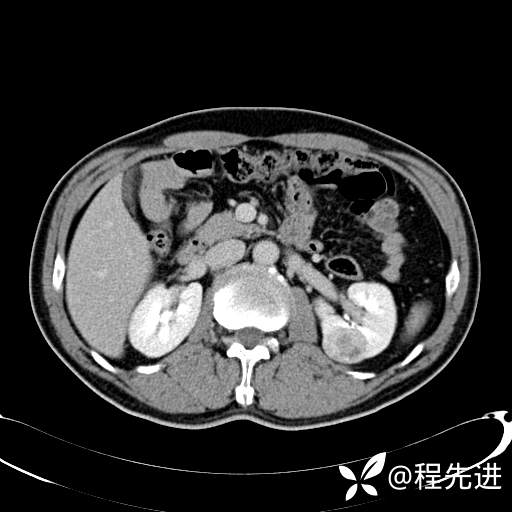

患者性别:男

患者年龄:65岁

简要病史:腰痛2月,体检发现左肾占位5天

皮质期: